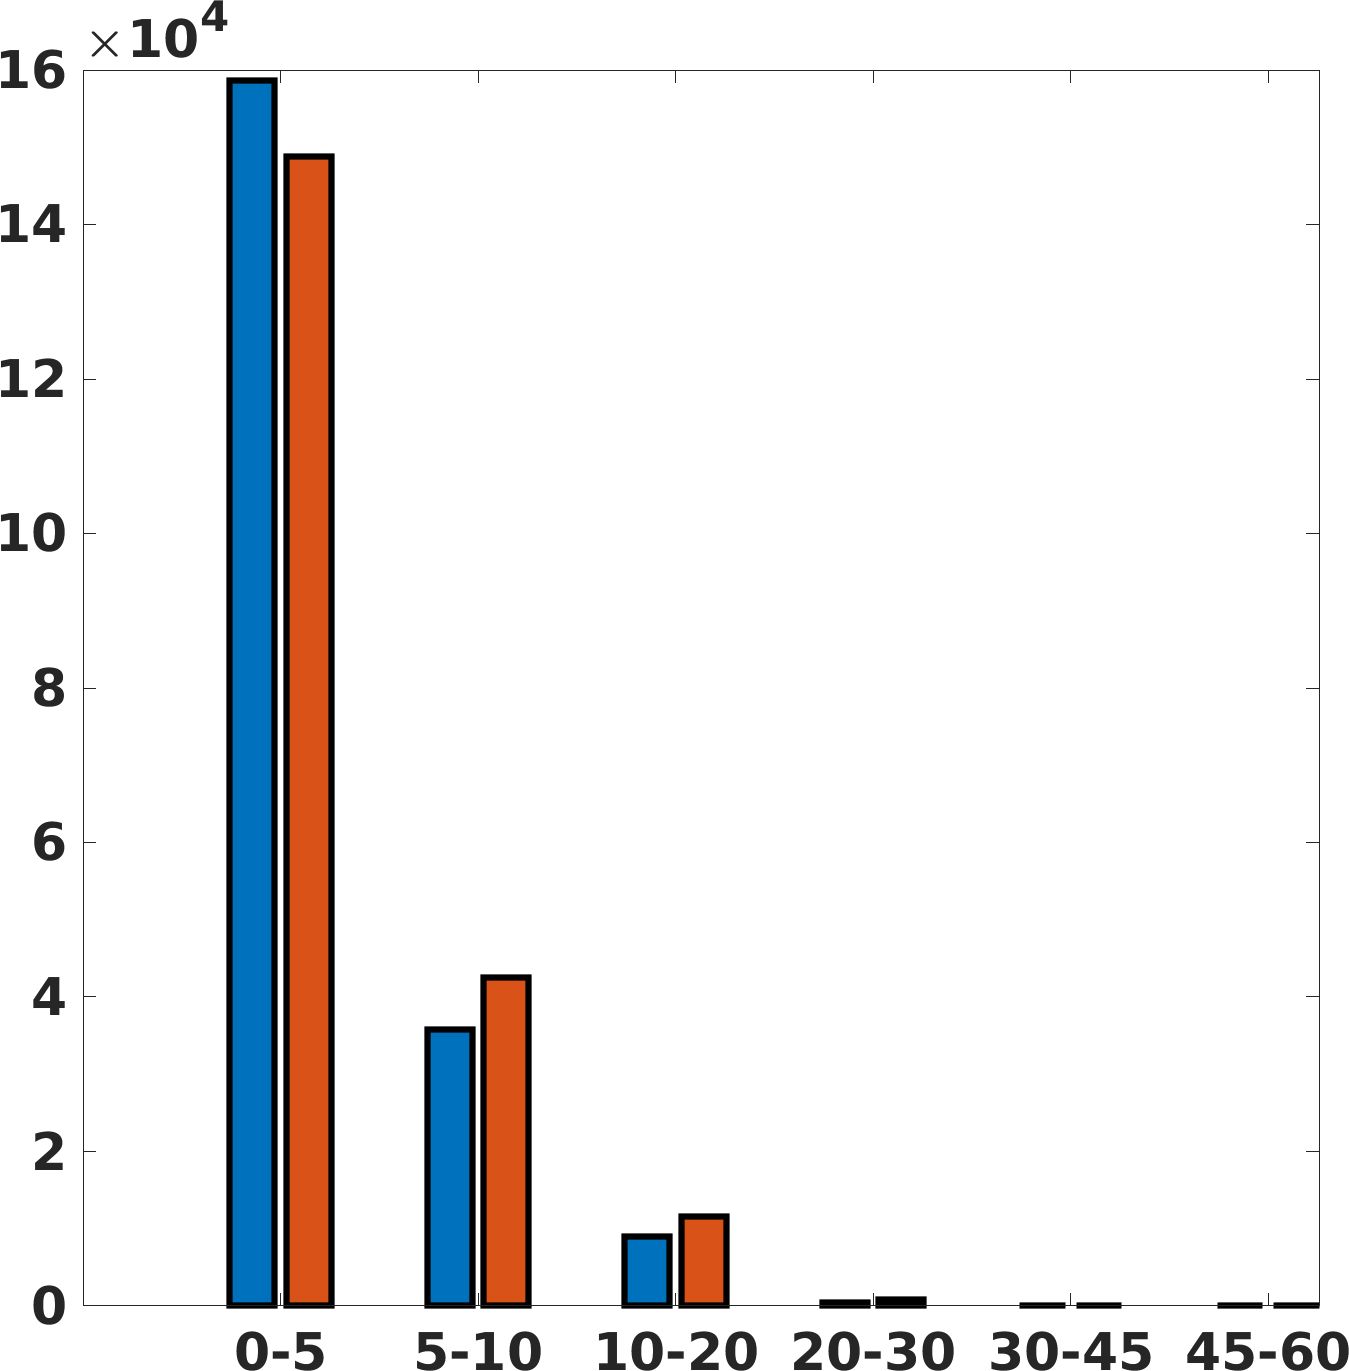

Fig. 7(a-b-c, right) shows the histogram of the absolute value of the error with respect to the target image, of the prediction and Cubic convolution results, respectively. The histograms show the number of pixels where the prediction error is lower than 5 (i.e., the first bin of the histogram), which means very similar to the target when visually analysing the images. From the Cubic convolution to the predicted images, this value increases of on obstetric 4X raw images, on cardiac 4X raw images, and on abdominal 4X raw images.

Fig. 8 shows the box plot of the SSIM (a-b-c, left) and MAE (a-b-c, right) quantitative metrics, as performed for PSNR metric. Also, these metrics show that our method improves the results of Cubic convolution both in terms of average value and variability. For example, the SSIM median value improves of on obstetric 4X images and the MAE median value improves of on cardiac 2X images.

Fig. 17 (right) shows the histogram of the absolute value of the error with respect to the target, of the prediction and Cubic convolution respectively. This result shows that our framework increase of and (2X and 4X, respectively) the number of pixels where the prediction error is lower than 5, which is very similar to the target when visually analysing the images, and improved with respect to the learning framework applied to raw images. According to Fig. 18, our method improves the accuracy of Cubic convolution. For example, the SSIM increases of on cardiac 2X and the MAE increases of on abdominal 4X.